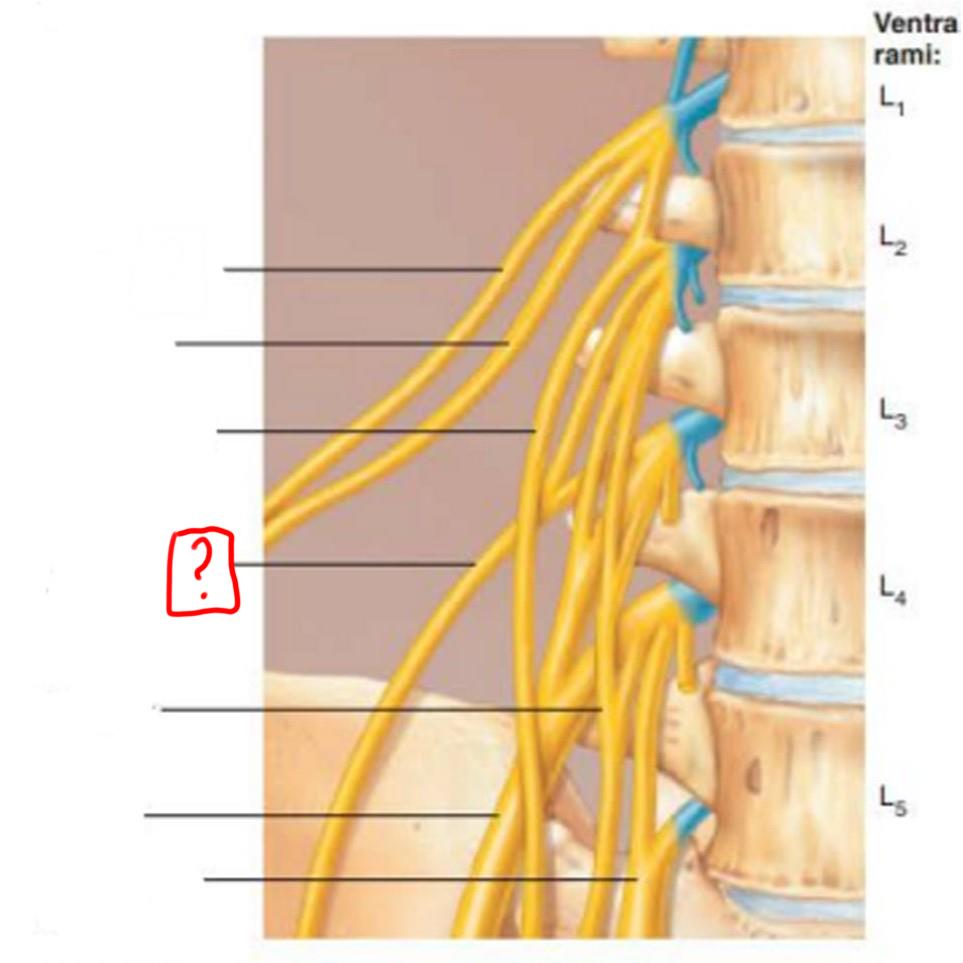

lumbar plexus

L1-L4

major nerves: ilioinguinal, obturator, femoral, genitofemoral

iliohypogastric

ilioinguinal

genitofemoral

lateral femoral cutaneous

obturator

femoral

lumbosacral trunk